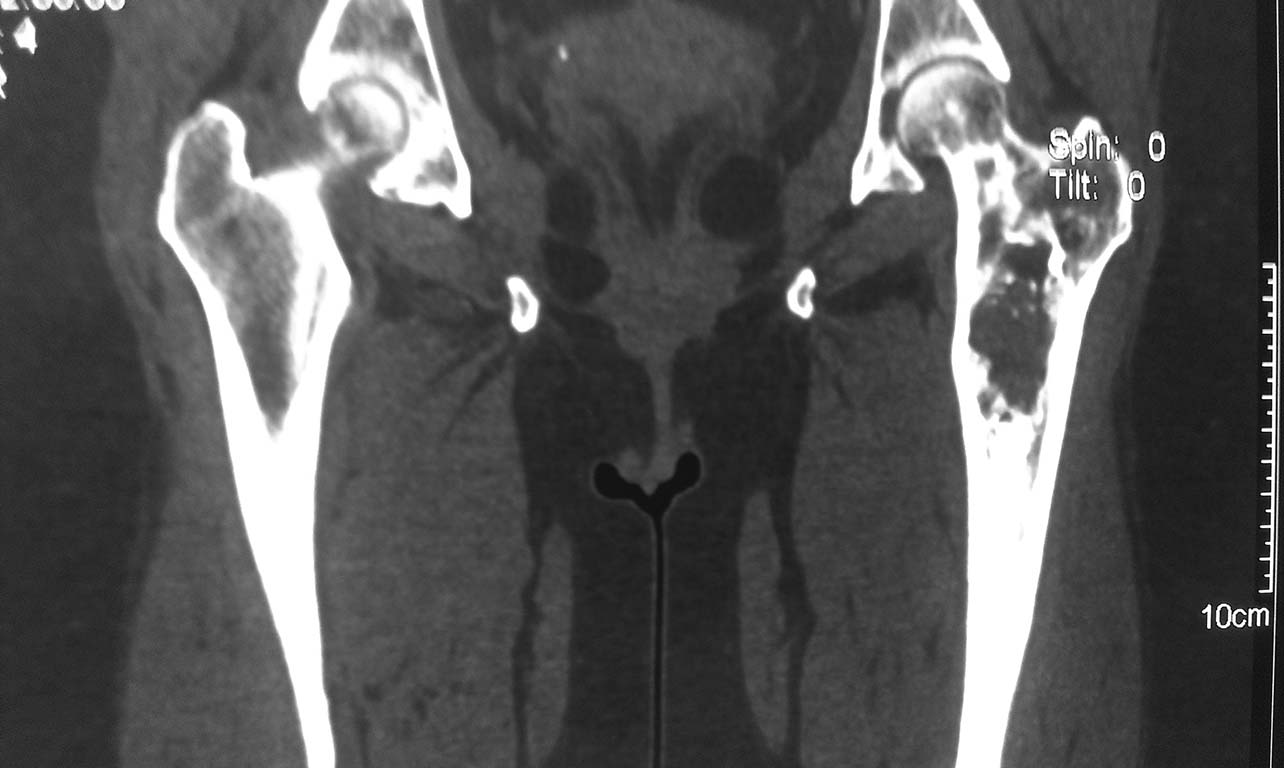

Пациентка 1952 г.р.  (61 лет), поступила жалобами: на непостоянные боли

в области левого тазобедренного сустава, верхней трети бедра и суставов

конечностей.

Anamnesis morbi: Со слов пациентки болеет в течении 2,5лет, когда

появились боли в бедре и крупных суставах. Об-но: по внутренним органам

без особенностей. Пальпаторно отмечается болезненность в проекции

верхней–  средней трети левой бедренной кости.

04.09.13г 1-м этапом произведена: Операционная биопсия из проксимального

отдела левой бедренной кости. Заключение патолого - гистологического

исследования: Дегенеративное поражение костной ткани с замещением

незрелой фиброзной тканью. В анализах в пределах нормы.

Резекцию проксимального отдела левой бедренной кости. Тотальное

цементное эндопротезирование левого тазобедренного сустава модульным

имплантом.